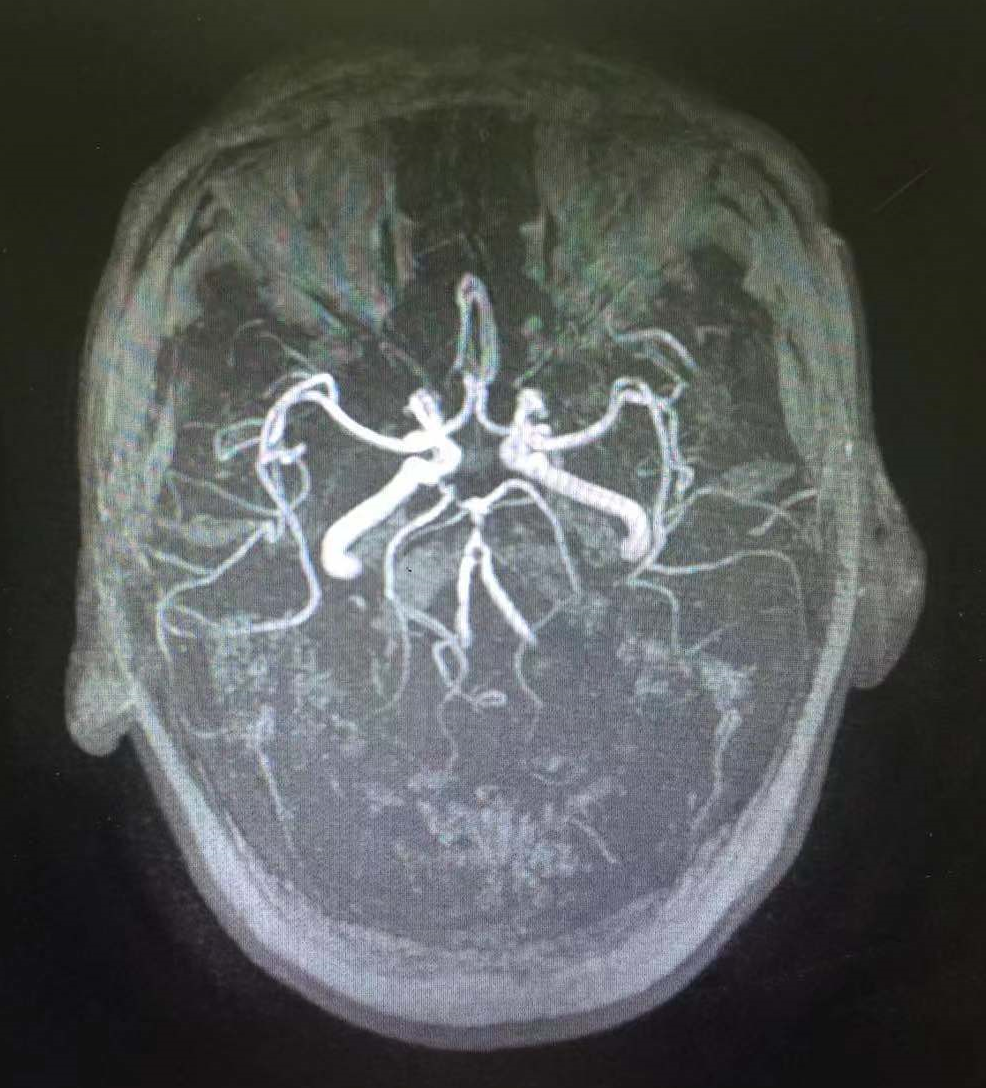

目前患者神清,可正确应答,左侧肢体肌力1级,积极康复治疗中。术前CT(图10),术后第四天CT(图11)。

图12 患者术后4天MRA提示血管通畅